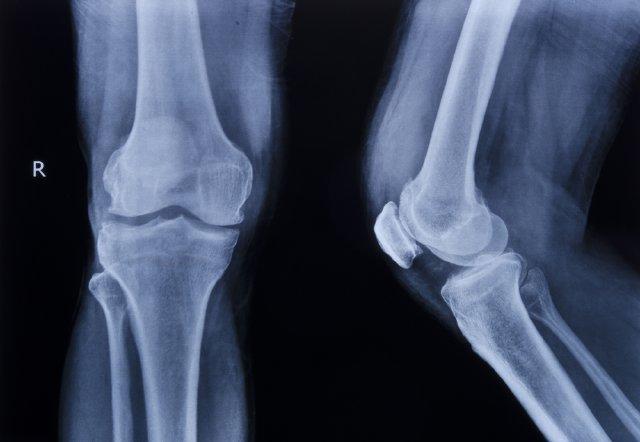

Това е най-разпространеното заболяване на костите. Характерно за него е намаляване на масата на костното вещество, като резултат от това се повишава чупливостта на костите и нараства рискът от счупвания /фрактури/. Загубата на костната маса настъпва сравнително бавно и почти незабележимо. Често едва появата на фрактури разкрива съществуването на остеопорозата.

Най-характерна проява на остеопорозата са костните счупвания. Типичните места са три: гръбначните прешлени, шийката на бедрената кост и китката. Честота им нараства прогресивно с възрастта. Остеопорозните фрактури могат да доведат до инвалидност и влошаване на качеството на живот.